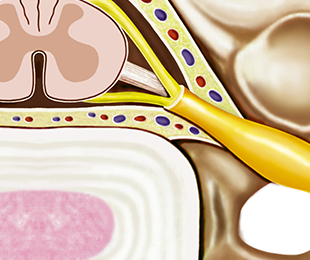

정확한 변소 부위에 도달한 치료제가 디스크와 신경 사이의 염증을 제거해줍니다.

유착이 박리되고 부어있던 신경이 겉으로 드러남

05

2차로 염증을 가라앉히는 약물을 투여

06

3차로 유착 재발을 방지하는 약물을 투여

07

신경의 유착이 사라지고 염증이 가라앉음

08

신경이 회복되고 통증이 완화됨